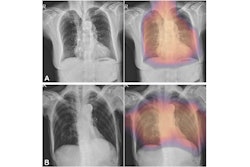

Neuromorphic AI leverages the firm's hyperdimensional computing and deep-learning technologies to assist radiologists and healthcare providers in diagnosing multiple chest conditions from x-ray images. Key features include an advanced spatial transformer network designed to improve the precision of image analysis and hyperdimensional computing encoding for pattern recognition and multi-label classification, according to the company.